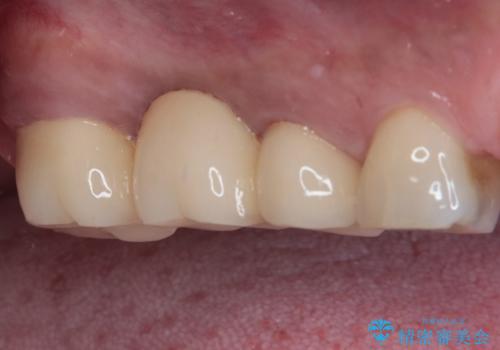

色が白いように思われましたが、今後クリーニングとホワイトニングを行っていきたいとのことでした。

銀歯が白い歯となったことはもちろん、クリーニングやホワイトニングにも関心を向けることができ、患者様には大変満足していただきました。